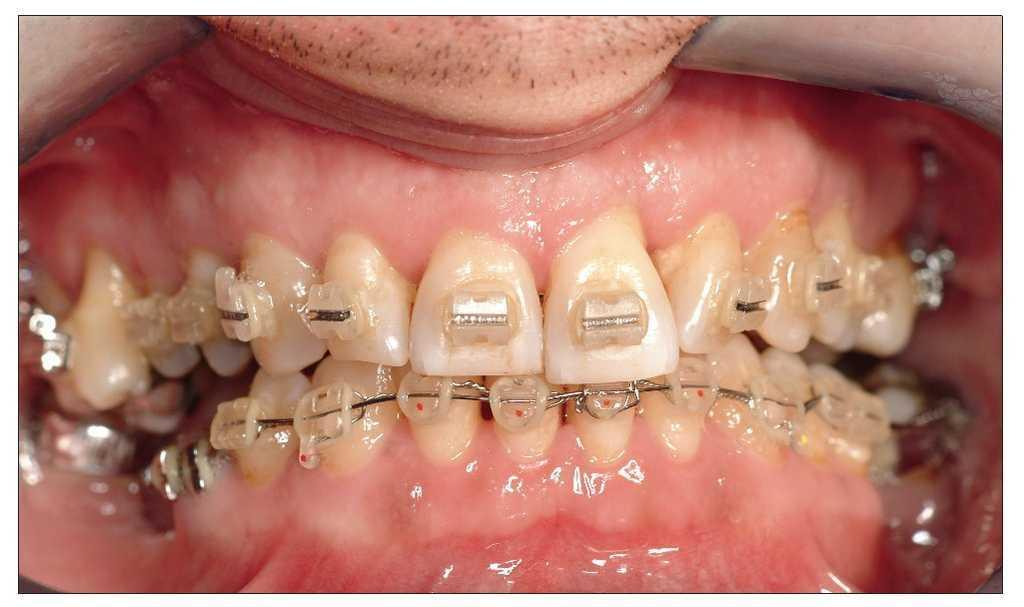

Figuras 6a a 6d. Situación clínica 1 año después de la intervención, 9 meses después de iniciar el tratamiento ortodóncico «activo».

Uno o dos años después de iniciar el tratamiento, el cuadro es clínicamente y radiológicamente estable con una ganancia de inserción clara y profundidades de sondaje fisiológicas incluso en los dientes 31 y 21, cuyo pronóstico inicial era desfavorable (figs. 7 y 8a a 8c). El odontólogo que derivó al paciente puede asumir a partir de este momento el tratamiento restaurador posterior.

Figura 8. Situación clínica dos años después del inicio del tratamiento: se aprecia un periodonto estable sin alteraciones.